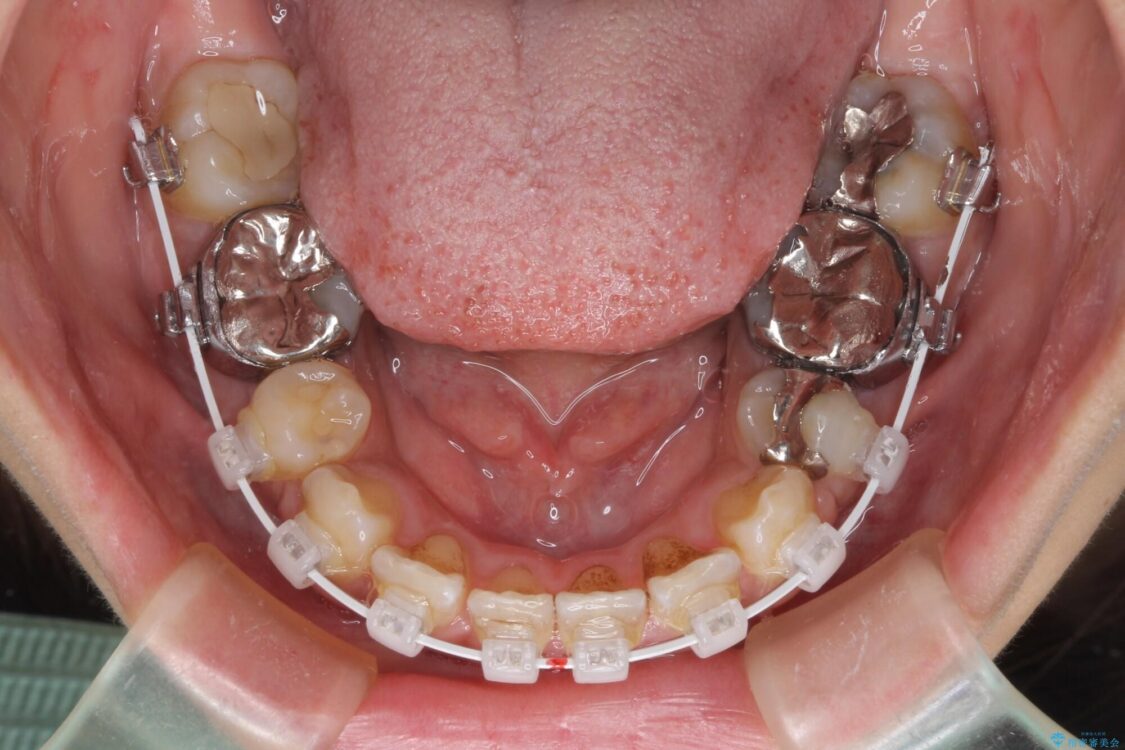

前歯のデコボコと上顎の前突感による口の閉じにくさを気にして来院された患者様です。

目立たない装置を希望されたので、上顎が裏側装置のハーフリンガルを選択し、上下左右の小臼歯(計4歯)を抜歯して矯正治療を行うこととしました。

治療途中

• デコボコと口元の突出感 ハーフリンガルでの抜歯矯正 治療途中画像